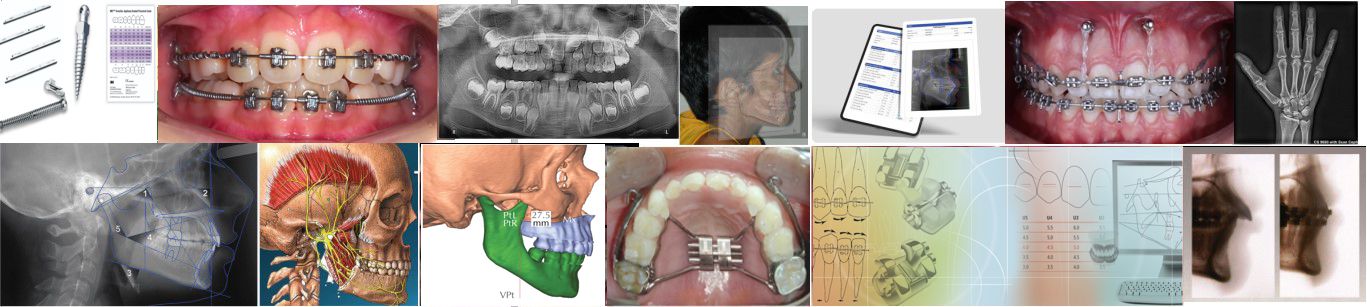

ORTHOPROGRESSIVE nació como un proyecto de código abierto en 2012 con la clara convicción de que la ortodoncia no solo trata los dientes, sino un conjunto de sistemas interconectados que no deben ignorarse. La terapia Bioprogresiva es más que una técnica es una filosofía que busca la armonía, función y estética, respetando los tiempos y las necesidades biológicas de cada paciente. Al mismo tiempo, integra todos los avances tecnológicos disponibles para los ortodoncistas modernos.

Diagnóstico estructural y funcional , enfoque cefalométrico.

Orthoprogressive tiene un enfoque integral que enfatiza la importancia de los planes de tratamiento individualizados, cuantificando las alteraciones a través de la cefalometría.

Principios fundamentales y uso de aparatología específica

Orthoprogressive adopta los últimos avances tecnológicos, partiendo de la premisa de fuerzas ligeras y otros principios fundamentales . No siendo necesario realizar cambios de protocolo en sistemas de alineadores, alambres súper elásticos, aparatos ortopédicos, brackets autoligados y de baja fricción, etc, serán nuestras herramientas de precisión y eficiencia en tratamientos en pacientes con dentición tanto mixta como permanente.

Siguiendo la trayectoria de algunos líderes contemporáneos como el Dr. Ronald Roth, Hugo Trevisi (MBT), los brackets de baja fricción y la ortodoncia y los alineadores invisibles, sus objetivos están indicados para la dentición permanente y poco o nada se dice sobre los tratamientos tempranos en dentición mixta. Es por ello que la motivación del autor es incluir toda la nueva tecnología en ortodoncia con la filosofía bioprogresiva. Debo mencionar el aporte del Dr Thomas Pitts al reducir el diámetro de slot de sus brackets y sus arcos super-elásticos termoactivados , lo que proporciona control tridimencional en etapas tempranas del tratamiento, que es uno de nuestros principios y que se desarrollaran mas adelante.

Cefalometría